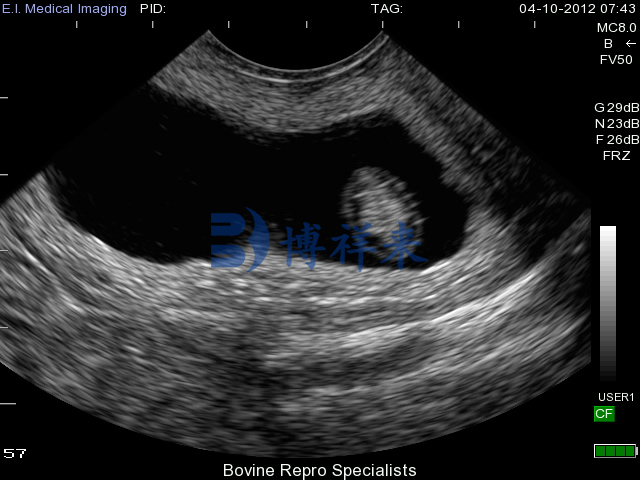

凸阵直肠探头测牛35天超声图

在牛用B超机的妊娠检测或生殖系统检查中,凸阵直肠探头的优势体现在:

视场更大,能够在单次扫描中覆盖更大区域,适合对整个子宫或更深部位的结构进行概览式观察。

较低频率使得声波有更好的深度穿透能力,因此在较深妊娠阶段(如妊娠中后期检查)或需要观察更深层组织时表现更稳定。

对于繁殖疾病等更复杂检查的需求,凸阵探头常被推荐用于扫描更广范围或对深部结构进行成像,以便全面评估结构状态。